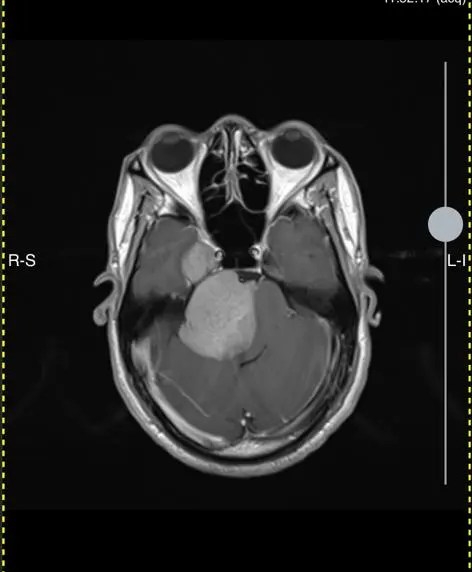

The work we do

S.T.D Neurosurgical Health Centre